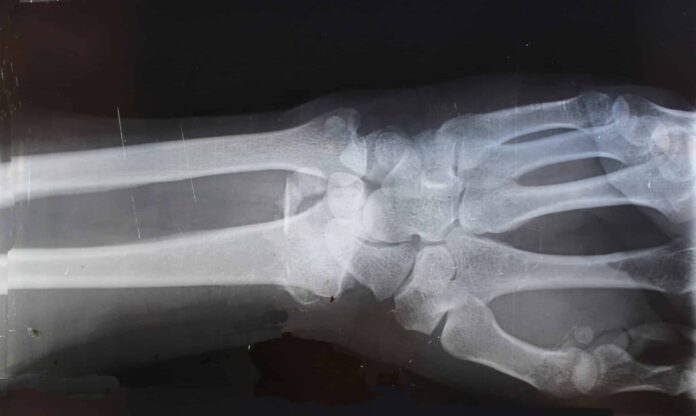

Новые научные разработки, поддержанные грантом РНФ, вдохновляют на оптимистичный взгляд в будущее борьбы с болезнью Кашина-Бека и другими патологиями, вызванными Т-2 токсином — агрессивным микотоксином, выделяемым грибами Fusarium. Заболевание отличается разрушением суставной ткани, и долгие годы оставалось загадкой для ученых до недавнего времени.